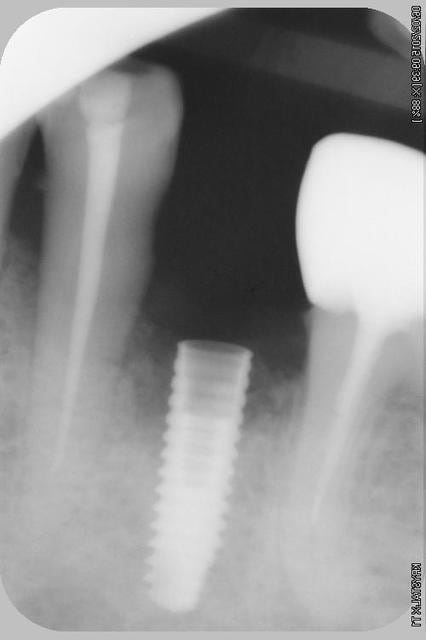

Nouveau patient, pose d'un implant il y a 2 mois....échec sans raisons particulières, douleurs et dépose.

Ce matin repose d'un nouvel implant et comme je ne veux pas prendre de risque, et que les dents adjacentes doivent être couronnées, je pose un bridge en emax press, mais scellé au ciment provisoire...

Si l'implant va bien le bridge sera déposé, coupé, et 44/46 seront collées définitivement après traitement acide et silane.

Si par hasard l'implant pose problème, dépose et bridge collé.

alors là pas du tout, le patient vient me voir pour des implants, donc je fais une étude du cas absence des molaires supérieures, couronnes mandibulaires très ancienne 45 racine cassée, 44 dévitalisée mais passablement déchaussée, donc avulsion de 45 et pose d'un implant avant de refaire les couronnes 46/47 et l'ensemble.

Échec implantaire, et oui ça arrive, même dans un cas paraissant simple.

Dépose gratuite bien sur et repose gratuite aussi, le bridge n'est pas facturé non plus, il le sera sous forme de 2 couronnes que cette fois ci l'implant fonctionne ce que j’espère, ou laissé en bridge si l'implant devait être retiré.

Le fait de scellé au ciment temporaire ne pose en principe pas de problème pour 3 à 6 mois.

Oui, un Px, le premier était un Reg.

l'os était tendre, ce qui explique le choix du Px